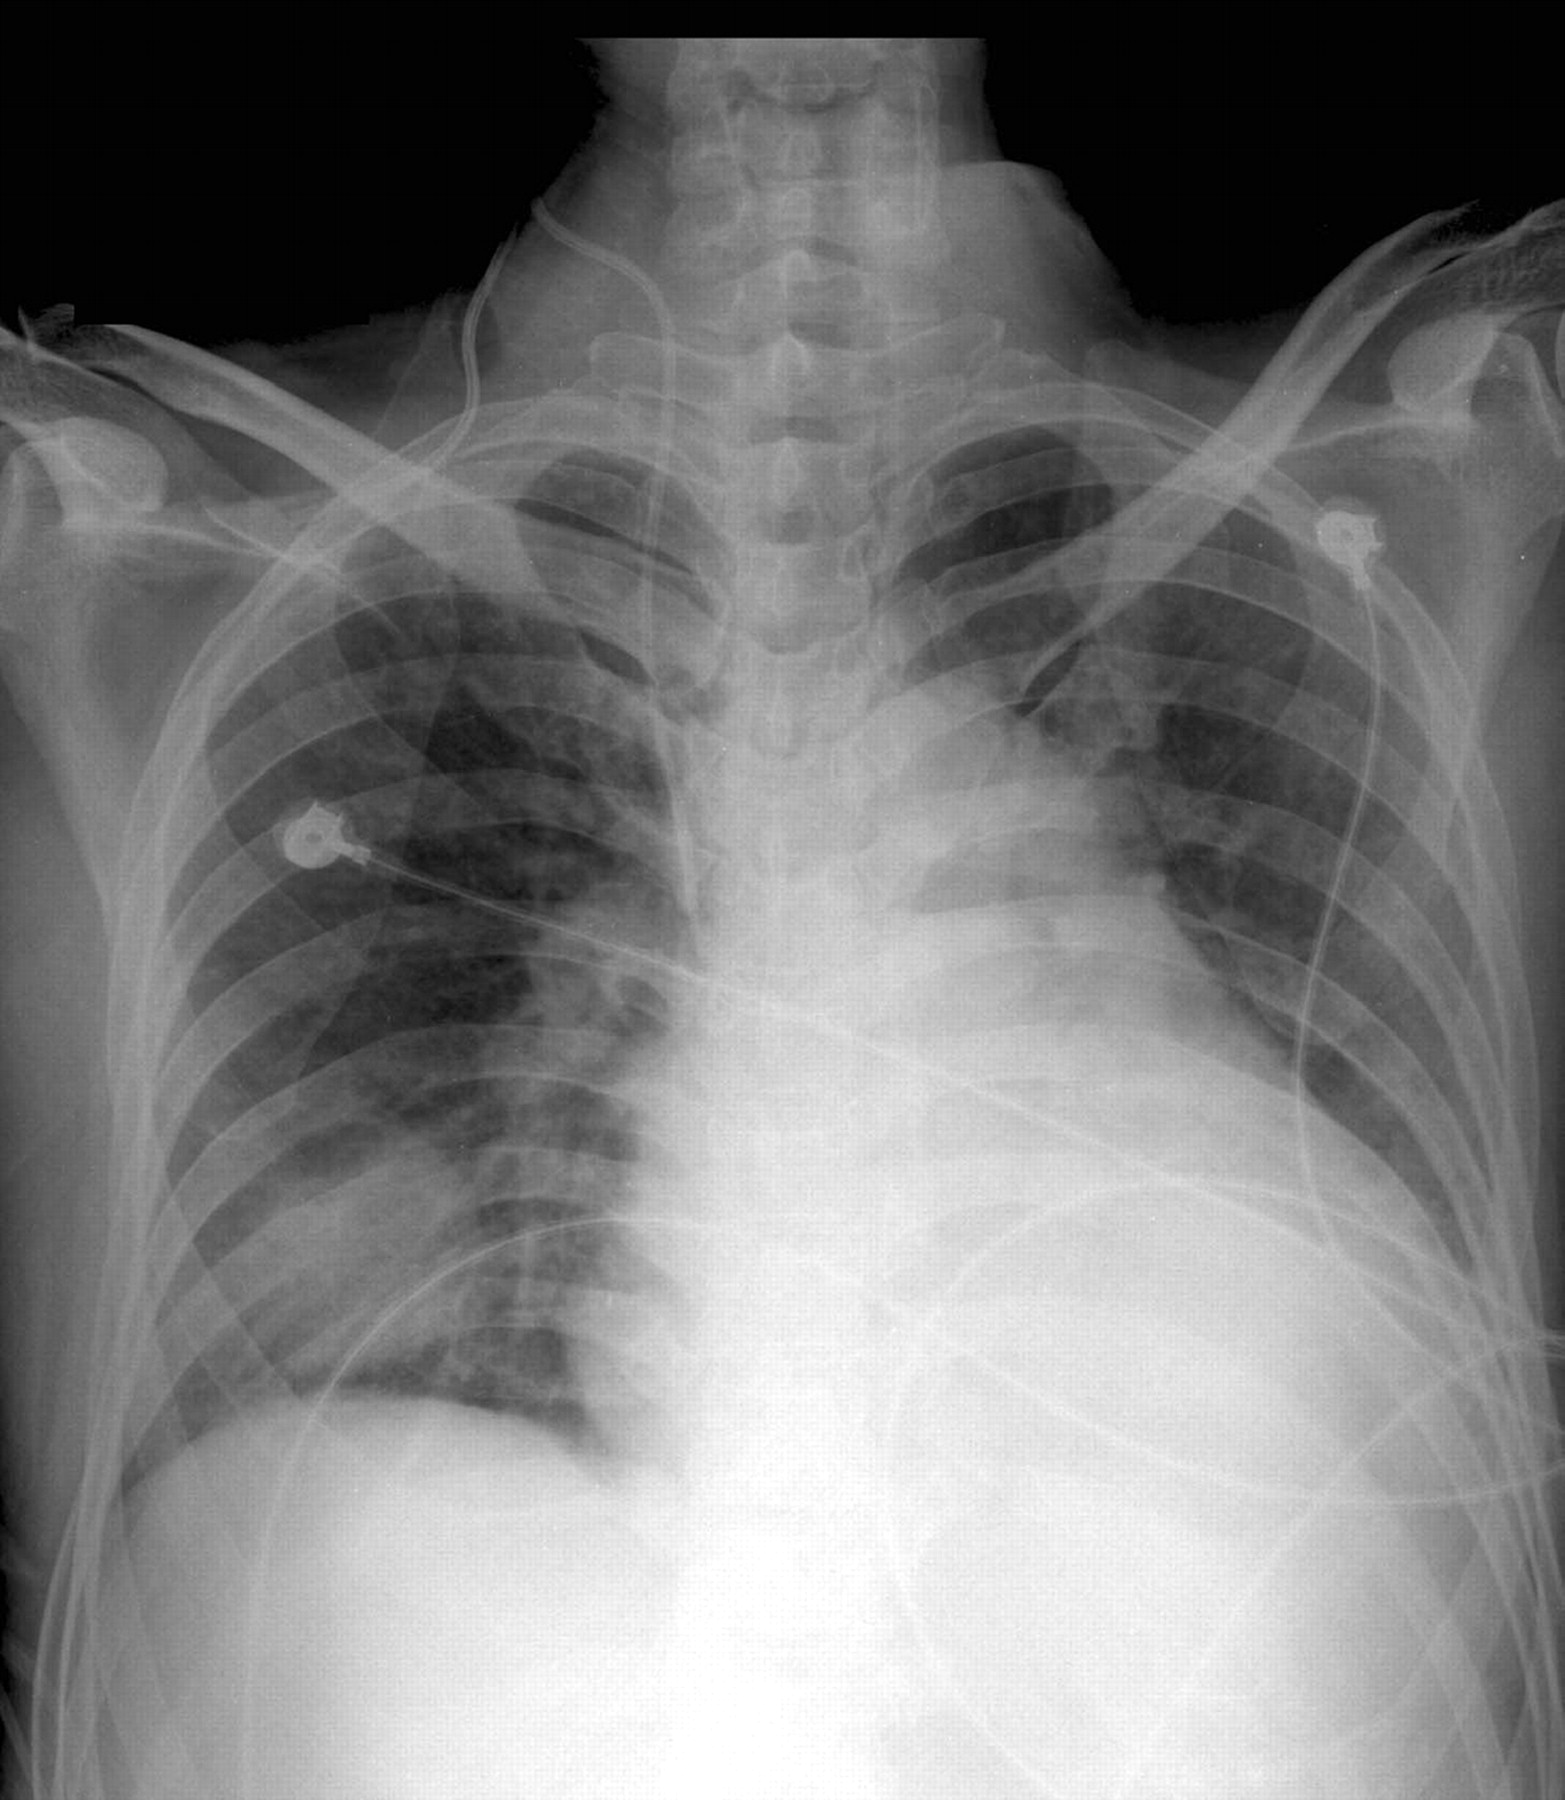

Central Venous Catheter Air Embolism . It is generally related to. Air embolism is a known risk with insertion, manipulation, and removal of central catheters, with a reported incidence rate of 0.03% to 2%. Air embolism is a potentially fatal complication of central venous catheter placement with a broad range of. During central venous catheter removal, several procedural techniques have been proven to decrease the potentially fatal. Air embolism is a rare but mostly iatrogenic complication of medical or surgical procedures and may have a serious outcome. A, massive arrival of air bubbles in right chambers of the heart 20 minutes after central venous catheter removal. Vascular air embolism is the entrainment of air (or exogenously delivered gas) from the operative field or other communication. We herein report a case of massive air entrainment from an inadvertently disconnected port of a central venous catheter.